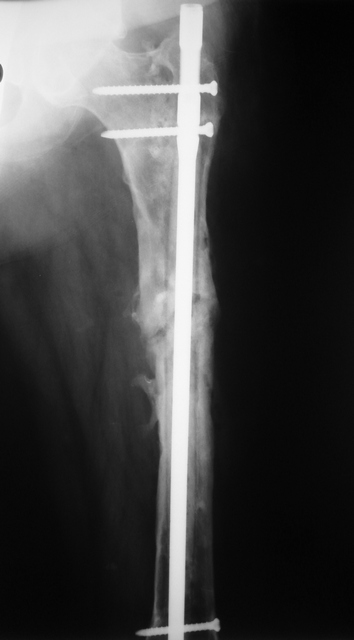

[Ortho] Proximal femoral shaft nonunion + osteomyelitis

Вчера наш пациент был на контрольном осмотре. Вроде все идет нормально. Рентгенограммы от 25 сентября 2007 г. (прошло 5 месяцев после операции) прилагаю.

Имя     : 2.jpg

Тип     : image/jpeg

Размер  : 57162 байтов

Url     : http://weborto.net:8080/pipermail/ortho/attachments/20070926/c7cc77e9/attachment-0003.jpg